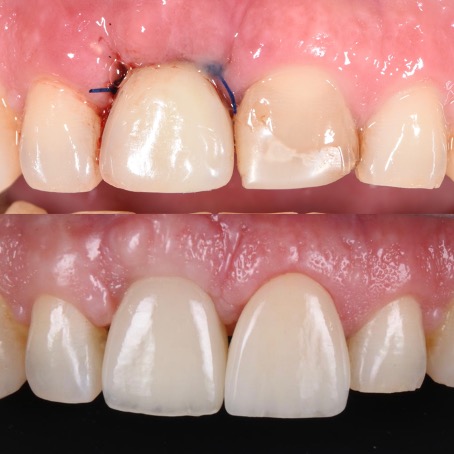

Cas esthétique d'implant unitaire

Mise en charge immédiate

Avec un implant unitaire et la mise en charge immédiate dans les zones esthétiques (quand c’est possible et selon le cas observé), la phase de cicatrisation, normalement de quelques semaines, se déroule avec une dent provisoire fixe (couronne provisoire vissée) qui permet d’éviter l’installation d’une prothèse provisoire amovible (dentier). Cela épargne aux patients de subir une intervention supplémentaire et il s’agit aujourd’hui d’une procédure standardisée, très confortable et très appréciée par les patients. C’est uniquement dans les cas exceptionnels, comme par exemple en cas d’infections aiguës, qu’il est préférable d’extraire d’abord la dent délabrée et de poser l’implant seulement lorsque l’inflammation est résolue.